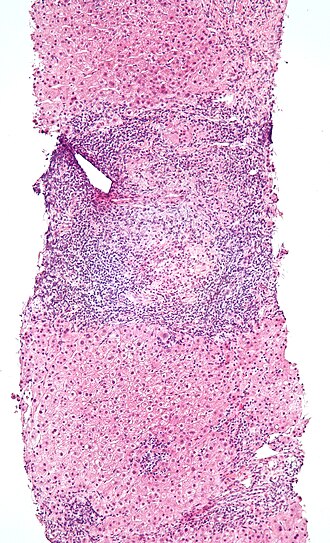

Primary biliary cirrhosis. H&E stain. | |

| LM | "Florid duct lesion": intraepithelial lymphocytes - in bile duct, bile duct epithelial cells with eosinophilic cytoplasm; plasma cells; +/-granulomas (close to bile duct); "Garland" cirrhosis -- has irregular border |

Microscopic

Features:

- "Florid duct lesion":[3]

- Intraepithelial lymphocytes - in bile duct - key feature.

- Bile duct epithelial cells with eosinophilic cytoplasm.[4]

- Plasma cells.

- Granulomas - close to bile duct.

- Seen in classic presentation -- often not present or poorly formed.

- Focal damage (may be missed on biopsy -- due to sampling).

- "Garland" cirrhosis -- has irregular border (unlike in EtOH).